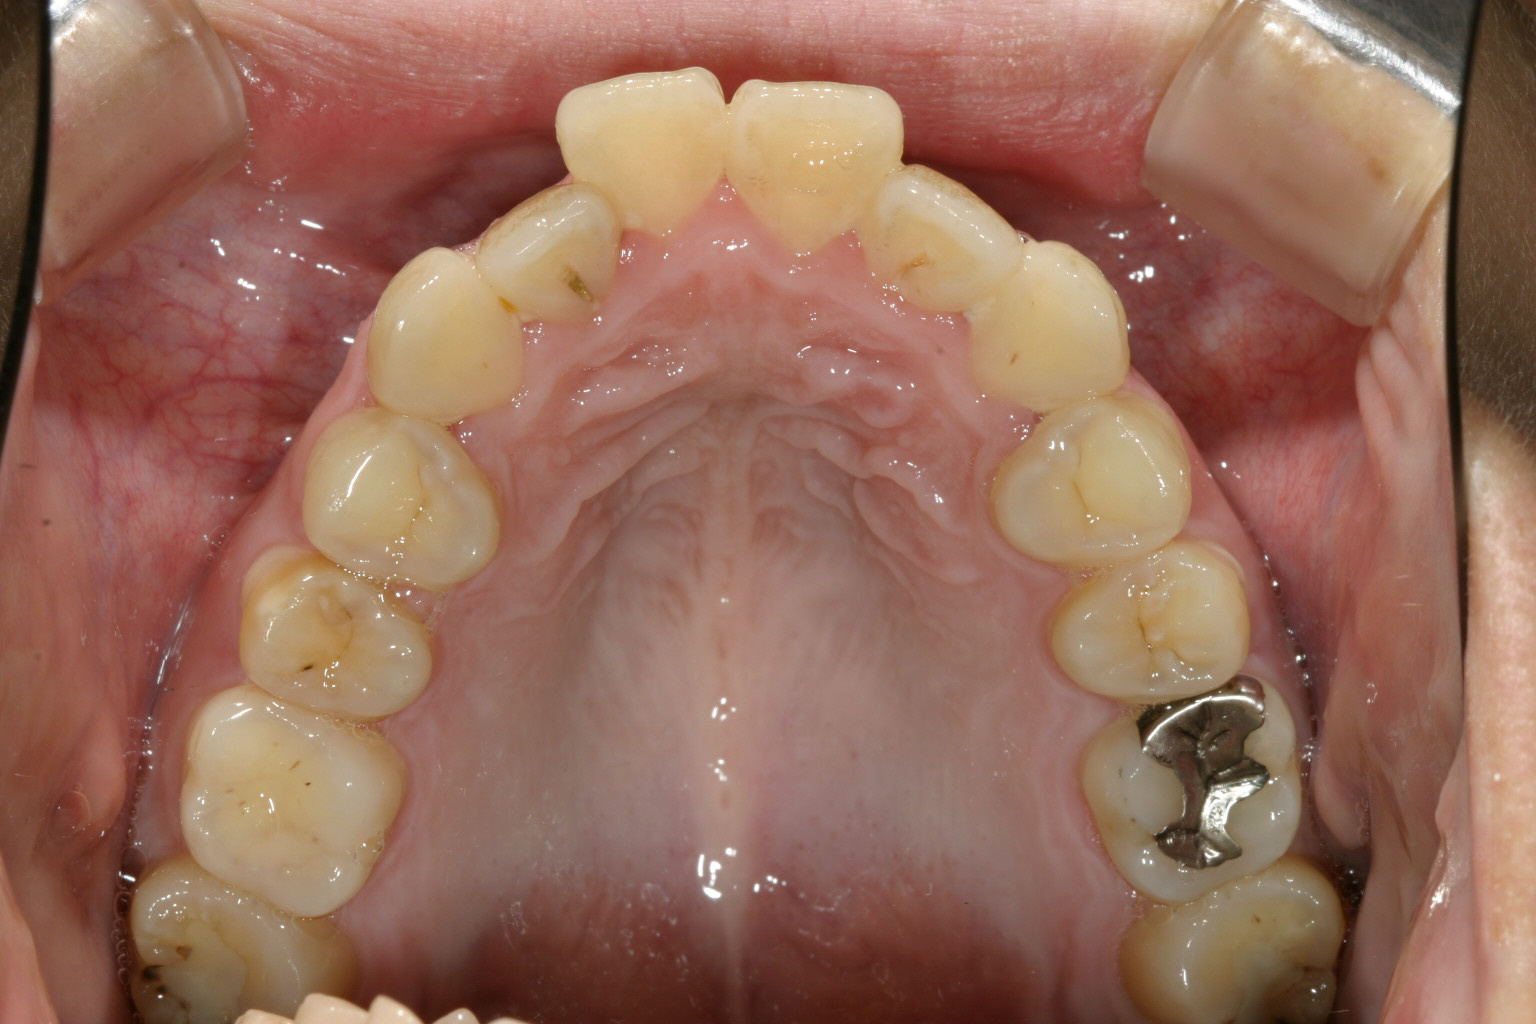

かなり前歯が出てますね~ 口元もゴボっと出っ張ってます。

下顎もアーチが狭い為に前歯にガタつきが見受けられます。